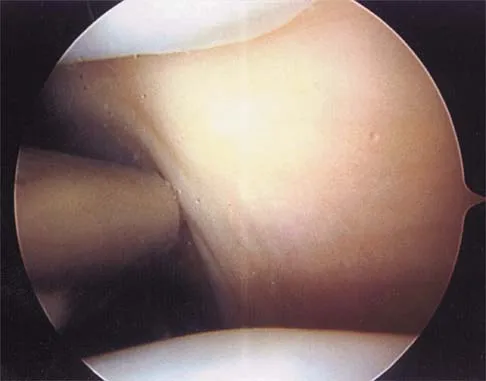

Question 81

A 28-year-old man sustained a shoulder dislocation 2 years ago. It remained dislocated for 3 weeks and required an open reduction. He now reports constant pain and has only 60 degrees of forward elevation and 10 degrees of external rotation. He desires to return to some sporting activities. An AP radiograph and intraoperative photograph (a view of the humeral head through a deltopectoral approach) are shown in Figures 31a and 31b. What is the best treatment option to decrease pain and improve function?

Explanation